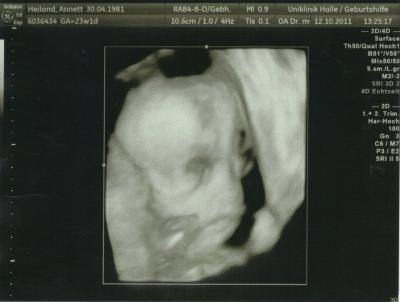

hallo ihr lieben. hatte ja heute mittag noch mal FD (zum 4. mal dieses SS ). also mit dem würmchen ist alles in ordnung. es sollten ja noch mal gesicht und wirbelsäule kontrolliert werden, da die das letzte mal nicht beurteilbar waren. aber dieses mal schon und es ist alles in ordnung. trotz das ich erst vor 3 wochen war und nur gesicht und wirbelsäule noch mal angekuckt werden sollten, hat er noch mal alles mit ausgemessen. hier mal die daten: BPD (kopf, scheiteldurchmesser) 54,4 mm FOD (kopf, vorne bis hinten) 72,3 mm KU (kopfumfang) 199,9 mm AU (bauchumfang) 170,0 mm FL (oberschenkel) 42,0 mm größe ist 29,4 cm mit einem gewicht von 525 gramm. dann wurde, weil wir es wollten, noch mal nach dem geschlecht gekuckt und es ist nichts mehr angewachsen, also bleibts (gott sei dank, wegen der wände die ich schon in rosa gemalt hab) beim mädchen. weil wir ja beim letzten mal leider kein bild vom gesicht machen konnten, hab ich dem arzt gesagt, wenn wir kein schönes bild kriegen, würde ich gerne eins vom geschlecht haben. da sagt der doch glatt "ahhhh, ein porno bild wollen sie haben" na ja, schlussendlich haben wir jetzt eins vom gesicht und eins vom geschlecht. als wir dann fertig waren sagte er noch zu uns, da die kleine schon so lange beine hat, können wir sie gleich bei germanys next topmodel anmelden, da passt sie dann gut rein, weil sie ja so groß ist alles in allem war es ein toller termin, sehr lustig mit dem arzt und ich bin froh, das alles ok ist und das es immer noch ein mädchen ist. das erste bild ist vom gesicht. auf den ersten blick siehts aus wie ein alien, man muss etwas länger hin schauen, da sieht man versteckt die kleine stubsnase, die nasenlöcher, die lippen usw. schaut einfach etwas länger hin. achso, die kleine sieht wie ihr papa aus, auf dem bildschirm haben wir es richtig gesehen. so das wars von mir. war ja nun lang genug. morgen noch mal FA besuch, vielleicht kriegen wir das gesicht morgen noch schöner hin. lg annett